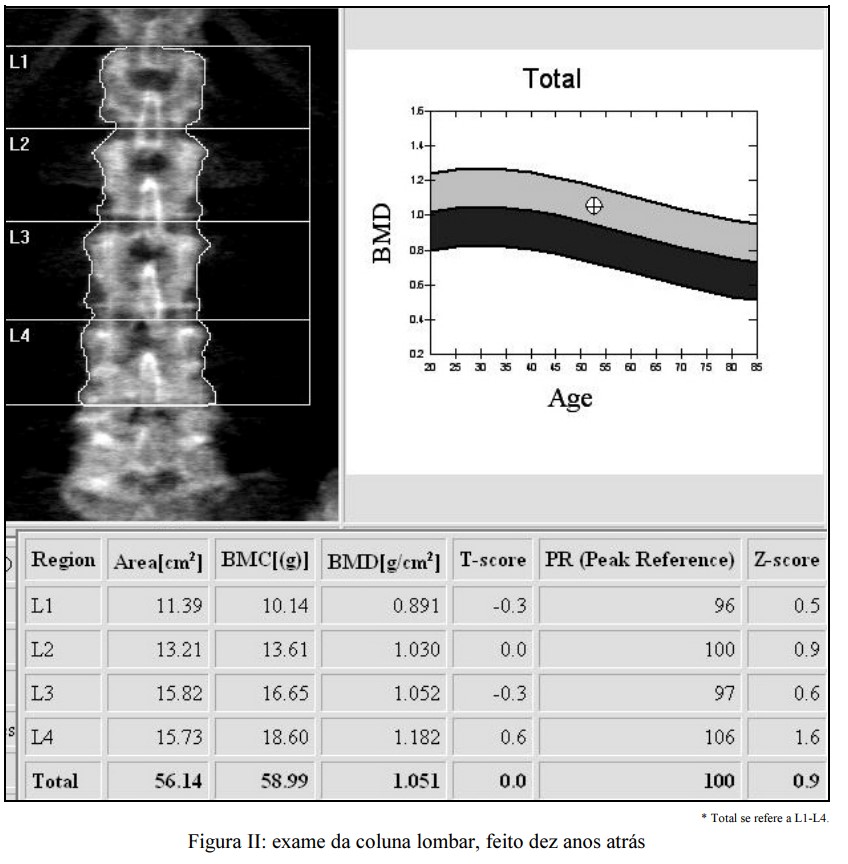

Na data marcada para pegar o resultado do exame de densitometria, o paciente procurou o médico radiologista e lhe apresentou a imagem, sem o respectivo laudo, de outro exame de densitometria da coluna e do quadril a que se submetera, em uma instituição desconhecida, havia, aproximadamente, dez anos, e solicitou laudo desse exame anterior e exame comparativo de densitometria.

Considerando as imagens e os dados do exame da coluna lombar do estado atual (Figura I) e do estado anterior (Figura II) e tendo como referência as orientações da ISCD (International Society for Clinical Densitometry) e da Sociedade Brasileira de Densitometria, redija um texto dissertativo relativo ao estudo do caso clínico acima apresentado, atendendo, necessariamente, ao que se pede a seguir.

< Interprete as imagens e o resultado do exame de dez anos atrás e cite os requisitos mínimos para o laudo inicial (de base ou primeira avaliação) de densitometria (DEXA/DXA). [valor: 16 pontos]